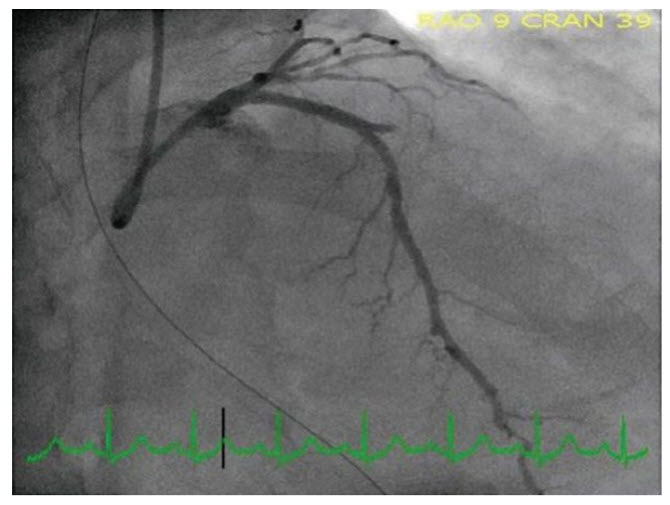

A 64-year-old man presents with ST elevation and is taken for primary angioplasty (see Fig. below).

Identify the infarct-related artery?

A. LAD

B. Diagonal

C. RCA

D. Left Circumflex

E. Obtuse marginal